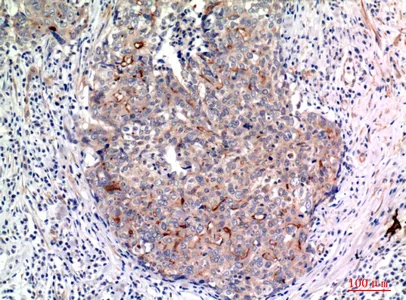

Mucin 1 Rabbit Polyclonal Antibody

Cat: APRab14238

Size1:50μl Price1:$118

Size2:100μl Price2:$220

Size3:500μl Price3:$980

Size2:100μl Price2:$220

Size3:500μl Price3:$980